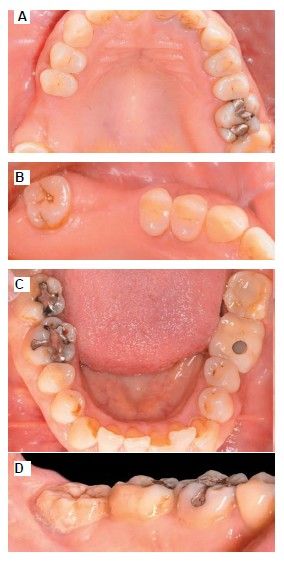

The medical history revealed no relevant medical or surgical antecedents, no known drug allergies, and no harmful habits. Intraoral examination revealed the absence of 1.6 and 1.7, and the presence of 1.8 and 4.8 (Figure 1). Radiographic examination using cone beam computed tomography (CBCT) revealed a residual height of 5.0 mm at 1.6, where an implant could be placed simultaneously, and 2.6 mm in the region of 1.7, making simultaneous implant placement with the lateral approach sinus elevation difficult (Figure 2).

Extraction of 4.8 was planned in order to use it as the donor tooth, for which informed consent was obtained in advance. An anaesthetic block was administered using 4% articaine (Inibsa®, Barcelona, Spain) with 1:100,000 adrenaline to the inferior dental nerve, the lingual nerve, and finally the buccal nerve. As the tooth had no associated infectious processes, only calculus was removed from the tooth using ultrasonic instrumentation and the extraction was performed as atraumatically as possible. The root surface was polished with turbine diamond burs under copious irrigation, thereby removing the periodontal ligament (Figure 3).